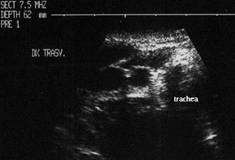

Se urmaresc rapoartele cu carotida, jugulara, muschii, traheea, esofagul.

Scintigrafia si CT aceluiasi pacient, metastaza laterocervicala stg ce impinge traheea spre dr.